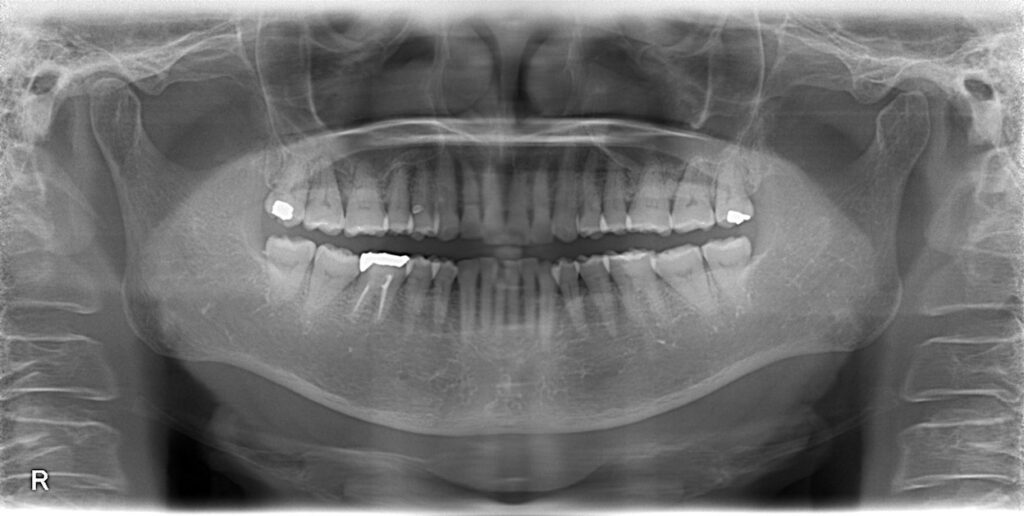

右上が痛い、ということで来院されました。

一見問題なさそうですが、歯周病の検査をすると右上の奥の歯に重度の歯周病が確認できました。

歯周病検査には専用の器具を使用すれば状態のほとんどを理解することは可能ですが、役立つのがCT検査です。

レントゲンではうまく描くことはできませんが、、、

CT撮影を行うと、歯、骨が立体で描かれます。

オレンジでマークしたところが黒く染まっているのがお分かりいただけるかと思います。

本来は白色〜鼠色で描かれ、骨があるべき部位です。